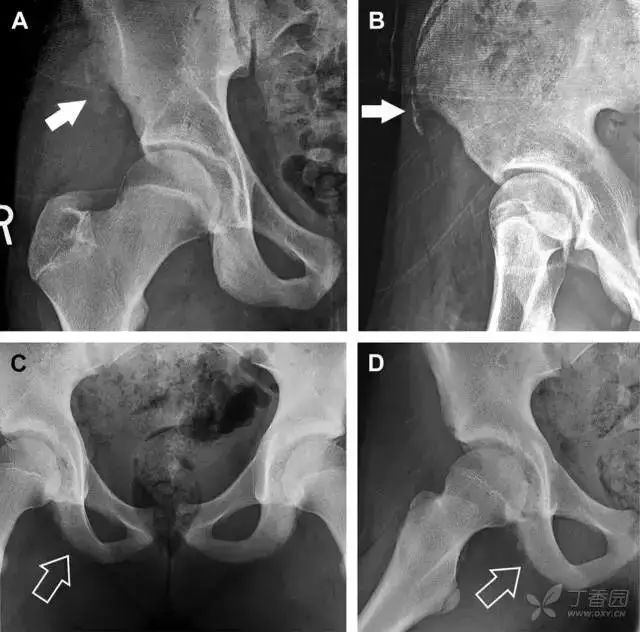

01髋臼骨折

髋臼骨折最常见的类型是髋臼后壁骨折,几乎占髋关节骨折的 1/4,且常常合并髋关节后脱位。由于骨性结构重叠,可能肉眼看上去觉得非常轻微的骨折,事实却并非如此。髋臼后缘中断常常是髋臼后壁骨折的一个特征(图 2)。

图 2 为髋臼后壁骨折伴髋关节脱位患者。A 右侧髋关节 X 线片示股骨头后方可见一骨折线(箭头),髋臼后缘中断。B 左侧髋关节 X 片对照可见髋臼后缘连续(箭头)。C  CT 三维重建图像示髋臼后壁缺损,可见旋转、移位的骨折块(箭头)

02耻骨骨折

具有持续损伤因素的耻骨支骨折,可能看似轻微,尤其是合并骨质疏松的患者。因此,特别需要注意皮质缺损和骨密度改变。长跑运动员易发生耻骨应力性骨折,常常发生在靠近耻骨联合的下支。由于这些骨折为非移位骨折,所以常常被忽视。

图 3 自行车事故患者,侧方受力的髋臼前柱/耻骨骨折。A 正位平片示右侧髂耻线轻微中断(实箭头),此处异常最初并未发现。此外,右下方其实还有一处轻微耻骨支骨折(空箭头)。B 10 天后行骨闪烁显像证实了髋臼前柱骨折和侧耻骨下支骨折(箭头)。值得注意的是,左侧前柱亦存在异常

03儿童撕脱性骨折

撕脱性骨折常在体育运动时由于肌肉强烈收缩引起。图 4 为容易发生儿童撕脱性骨折的部位。

图 4 儿童撕脱性骨折的危险区

图 5 儿童撕脱性骨折。正位片(A)和斜位片(B)示从髂前上棘撕脱的骨折碎片(箭头)。正位片(C)和另一个患者的蛙式位片(D)示右侧坐骨支皮质毛糙,腘绳肌腱撕脱损伤(如 C 和 D 空箭头所示)